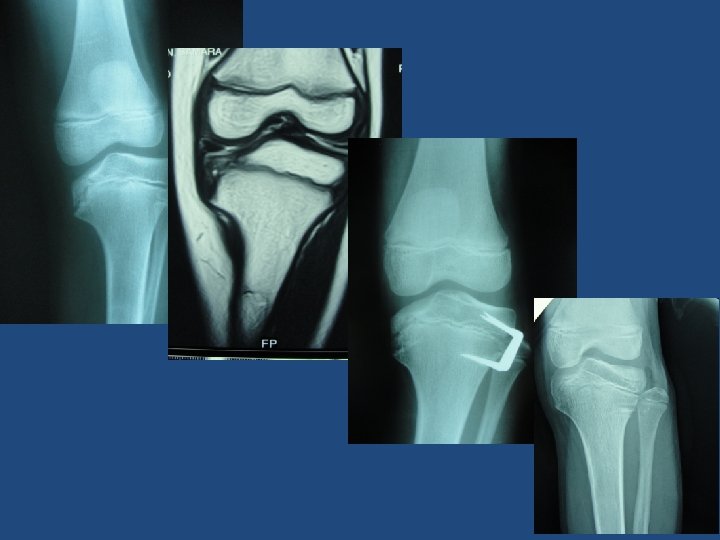

HISTORY In 2007 , Stevens proposed use of extraperiosteal nonlocking plate – Tension band construct – Long moment arm for correction • Hinges at edge of physis – Non rigid • Less concern of physeal arrest • Younger patients – One plate per physis

Why eight plates? Guided growth for angular correction Stevens JPO 2007

Goyeneche JPO 2009 Less extrusion in small children ( 8 -plates) Correction was achieved in less time with staples Longitudinal growth inhibition is lower with 8 Plates Correction of bone angular deformities : Experimental analysis of staples versus 8 - plates Goyeneche JPO 2009

Wiemann JM JPO 2009 63 limbs staples: 39 limbs eight plates: 24 limbs same correction rate same complication rate Physeal stapling versus 8 -plates hemiepiphysiodesis for guide correction of angular deformity about the knee JPO 2009

Eric Gordon et al Posna 2011 Angular deformity: 188 pts Staples: 189 limbs Eight plates: 66 limbs Same correction rate ( 60 vs 68 %) Eight plates : less complication rates

Jelinek Int Orthop. 2012 Both Blount stapling and the 8 -plate technique are methods for correction of genu varum and valgum deformity in skeletally immature patients A shorter operating time for implantation and removal was noted for the 8 -plate technique The 8 -plate versus physeal stapling for temporary hemiepiphyseodesis correcting genu valgum and genu varum: a retrospective analysis of thirty five patients. Jelinek EM Int Orthop. 2012